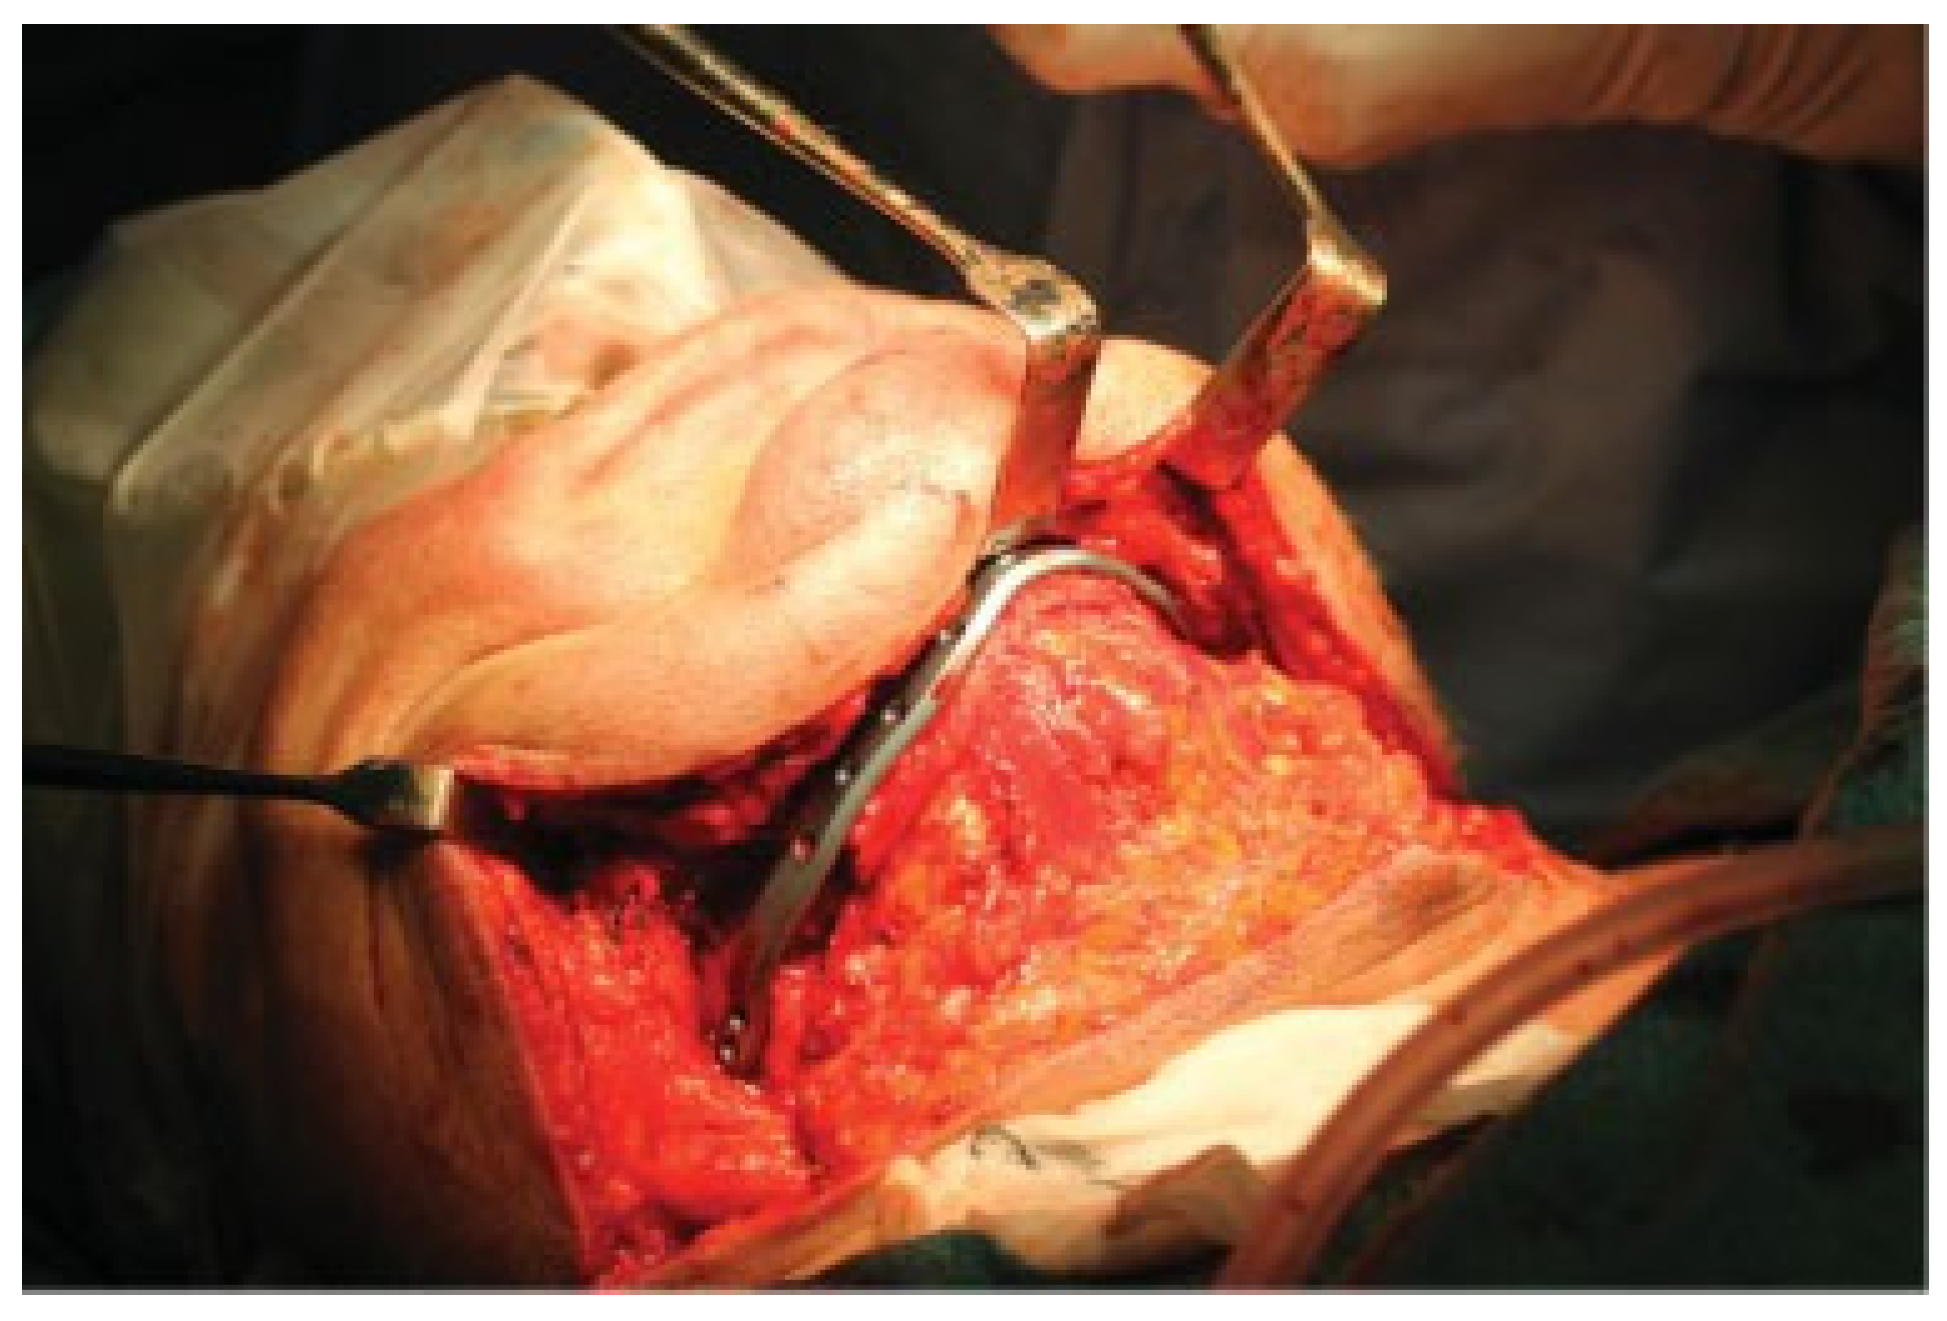

The secondary correction was performed via an extra-oral, wide exposure of the mandible (Figure 7). The failing osteosynthesis material was removed. The area of osteotomies (not needed to perform cuts due to bone resorption from infection) and screw-holes were outlined and placed with the help of the previously virtually planned surgical guides (Figure 8). The subject was placed in MMF with screws (Figure 9). The necrotic tissue was cleared out from the area of the fractures bilaterally. The open bite was corrected by the pre-planned rotations of the segments in the area of the virtual osteotomies and proper occlusion was established. By placing the subject in MMF, the rotations of the displaced segments were enhanced, these included 4 degrees posterior rotation of the two proximal segments and anterior rotation of the anterior segment to alignment of the mandibular border. The mandibular position was secured by the installation of the PSI-plate, displaying an exact fit to the mandibular border, and the already drilled holes and by placing the screws of planned length (Figure 5). In this way, holes and screws worked together as multiple guides in moving the segments into their planned correct position along a perfect match under the plate (Figure 10). An iliac-crest graft of cortico-cancellous bone was harvested and placed into the bilateral defects. Oral fistulas were closed and the wide flap over the neck was repositioned in layers using resorbable sutures in the sub-cutaneous tissue and with staples in the skin. MMF was removed and occlusion found in order as planned. Healing was thereafter uneventful and a stable situation and a good occlusion have been seen on all follow-ups until the latest at 10 months post-op (Figure 11, Figure 12 and Figure 13).

Figure 7.

Wide extra-oral exposure of the mandible, removal of plates and granular tissue in the fracture areas. Outcome model and PSI is displayed.